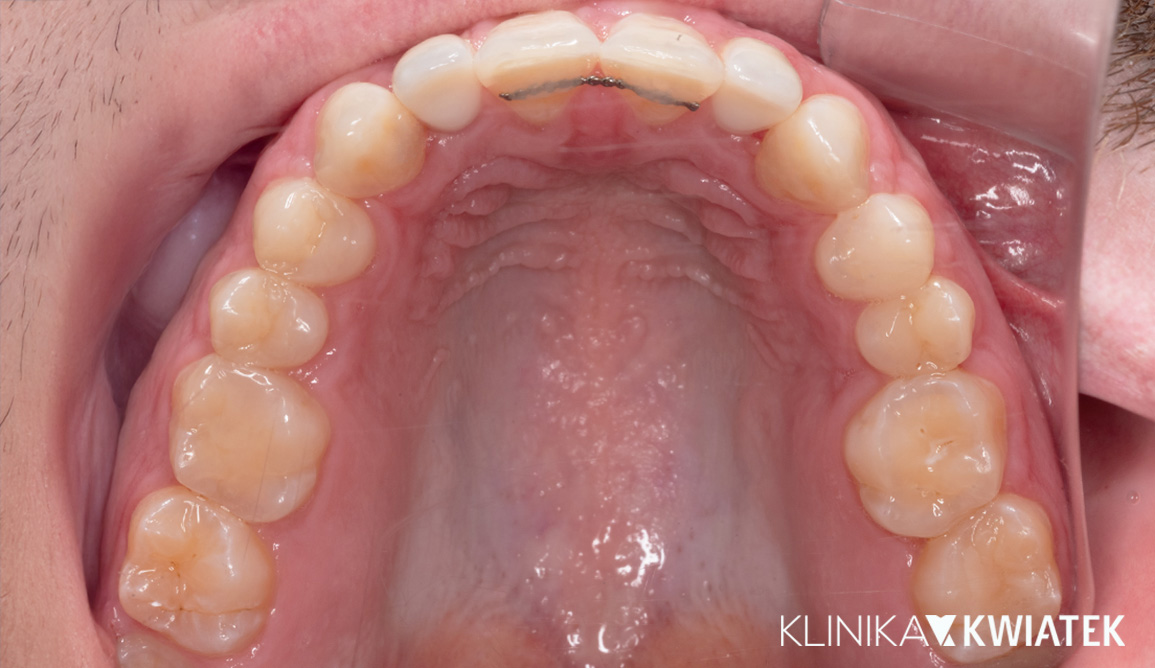

Jak uśmiech pokonał strach – metamorfoza pełna zaufania

Pacjent przez wiele lat unikał wizyt u dentysty z powodu silnego lęku. Strach przed leczeniem sprawił, że w jamie ustnej pojawiły się rozległe zmiany próchnicowe i liczne zęby wymagały ekstrakcji.

Po dokładnej diagnostyce i rozmowie, wiedząc, że Pacjent wyklucza leczenie ortodontyczne, krok po kroku wdrożono kompleksowy plan leczenia – od higienizacji i leczenia zachowawczego, przez zabiegi chirurgiczne i endodontyczne, aż po odbudowę braków zębowych na implantach.

Dziś Pacjent z dumą i spokojem uśmiecha się bez lęku – cieszy się zdrowym, estetycznym uśmiechem, stabilnym zgryzem i doskonałą higieną jamy ustnej.